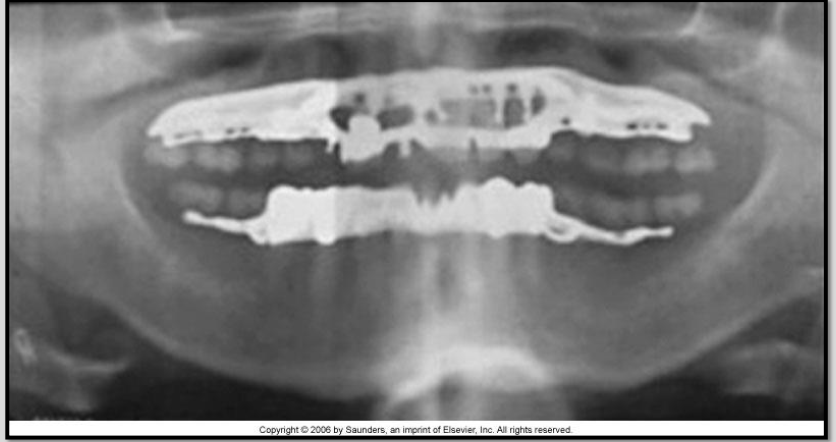

Describe partial dentures and their appearance on a radiograph.

Removable partial dentures (RPD)Â

have a metal base with acrylic saddles

appears densely radiopaque where metal is

slightly radiopaque in areas of acrylicÂ